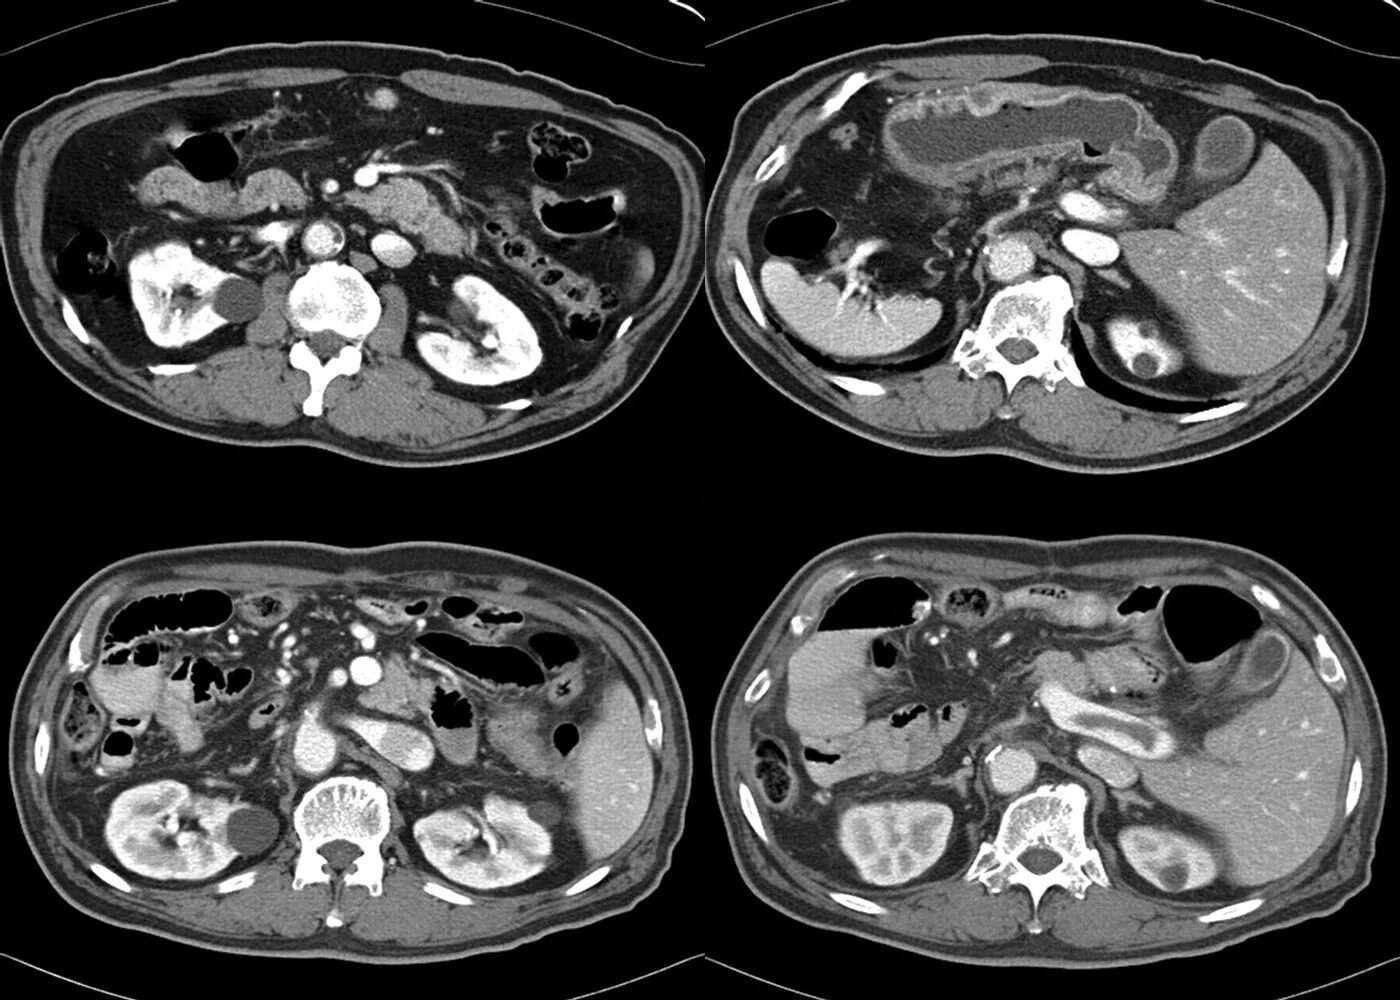

Что показывает мскт